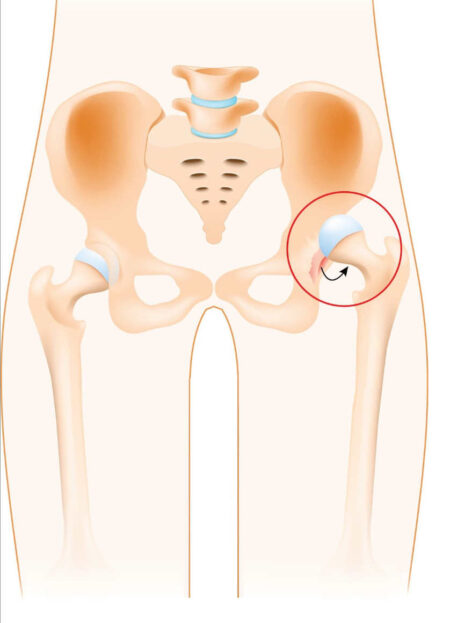

Poškodba Labruma

KOLKA

- razvojnimi nepravilnostmi (displazija kolka),

- utesnitvenim sindromom kolčnega sklepa (FAI),

- degenerativnimi obolenji,

- travmami (padec, udarec),

- preobremenitvami pri športu (ekstenzija in zunanja rotacija).

01. Simptomi poškodbe labruma

- Bolečina v dimljah, ki izžareva iz globine sklepa

- Klikanje ali zatikanje kolka

- Občutek nestabilnosti in okorelosti

- Zmanjšana gibljivost, predvsem pri večjih poškodbah

- Povečana bolečina pri aktivnostih ali dolgotrajni drži